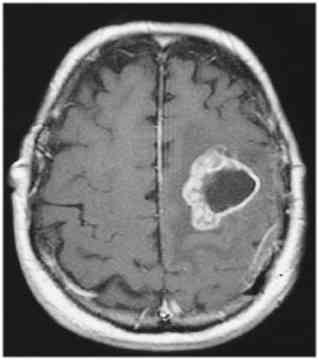

cavernoma

dilated vascular cavity lined by vascular endothelium

typically supratentorial

popcorn appearance on MRI, core can be hyperintense, dark rim on T2

can cause seizures, can bleed